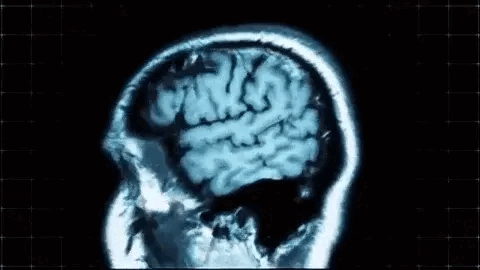

There is a problem, however. If the image is rotated, even slightly, the result changes. Imagine, for example, that we are dealing with MRI images and suppose that two different images, taken at different times, are available, such as the ones below.

If the goal is to identify small local changes, or even large overall differences, this will surely pose a problem. While image complexity is invariant to translations, this is certainly not the case for rotations.